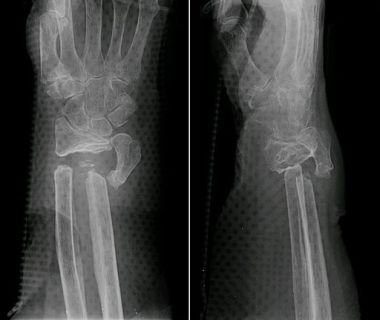

Klient w wyniku wypadku na motocyklu, zawinionym przez innego kierowcę, doznał skomplikowanego złamania ręki. Co prawda bezpośrednio po zdarzeniu przeprowadzono zabieg zespolenia kości ręki śrubami tytanowymi. Jednakże po kilku miesiącach okazało się, iż doszło do wykształcenia się w złamanej ręce tzw. stawu rzekomego.

Staw rzekomy, czyli nieprawidłowy zrost, czy raczej brak zrostu mogący powodować powstanie między rozdzielonymi w wyniku złamania kośćmi stawu, którego raczej tu być nie powinno.